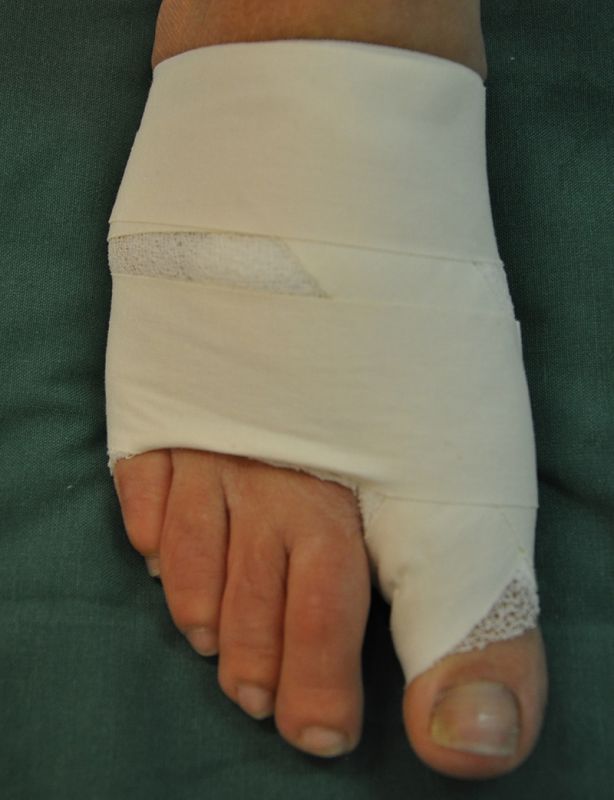

• Für das Anlegen des Spezialverbandes, entsprechendes Verbandsmaterial (sterile Kompressen, 4 cm Haftbinde, Pflaster oder Tapestreifen).

Nachbehandlung

• Vorfußentlastungsschuh für 2 Wochen, anschließend flacher Verbandschuh für weitere 4 Wochen.

• Verbandswechsel (nur vom Operateur selbst oder durch speziell geschultes Personal) 7, 14, 21, 28 Tage postoperativ mit Freigabe nach 6 Wochen.